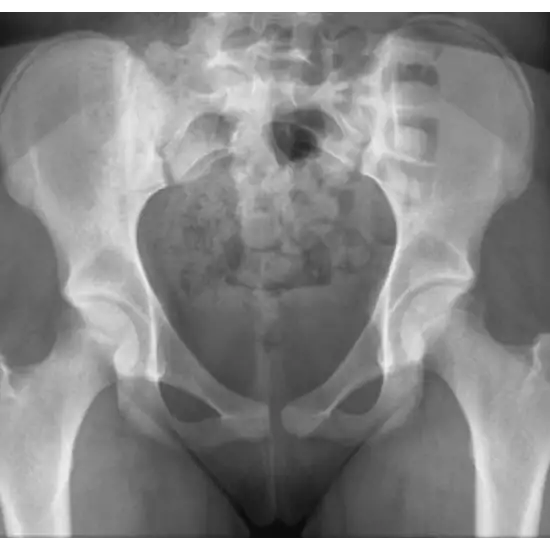

An X-ray of both hip joints AP View Test is utilized to visualize the pelvis, the bones of the hip joint, and the surrounding soft tissues (skin and muscles).

The doctor prescribes this test to diagnose any bone fracture that comprises the hip joint, monitor the healing of the broken bone after it has been set, and detect any infection, osteoporosis, deformities, or unusual bone growth.